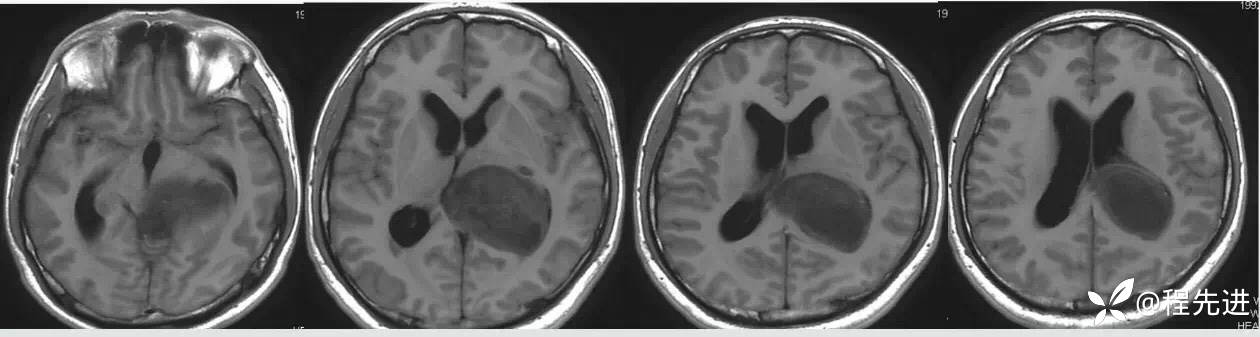

T1:

T2: